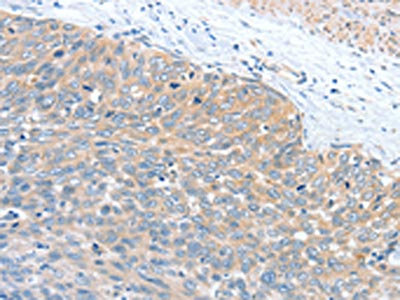

The image is immunohistochemistry of paraffin-embedded Human cervical cancer tissue using CSB-PA796998(WNT3A Antibody) at dilution 1/40. (Original magnification: ×200)

The image is immunohistochemistry of paraffin-embedded Human thyroid cancer tissue using CSB-PA796998(WNT3A Antibody) at dilution 1/40. (Original magnification: ×200)